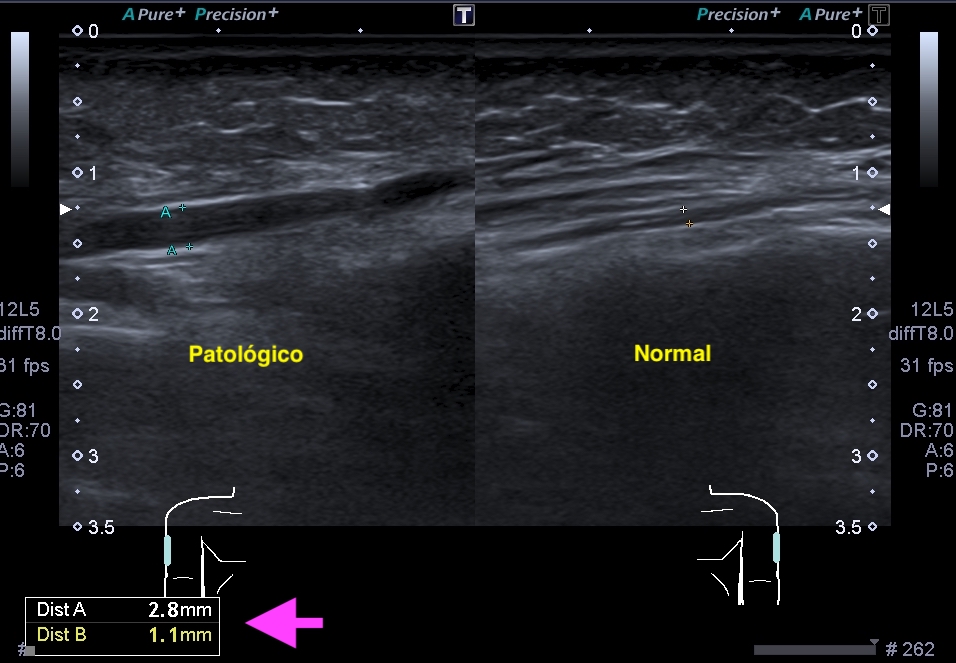

La radiografía revela aumento de las partes y se refrenda en la ecografía como puedes ver en la imagen aunque aún no hay afectación en el hueso en el caso que te presento hoy.

Ecografícamente y debido a su levedad, en el caso de hoy solo observamos cambios en las partes blandas de la cara lateral de la cabeza del quinto metatarsiano, este tejido se muestra heterogéneo, la cortical del hueso ligeramente prominente sin afectación de la misma.